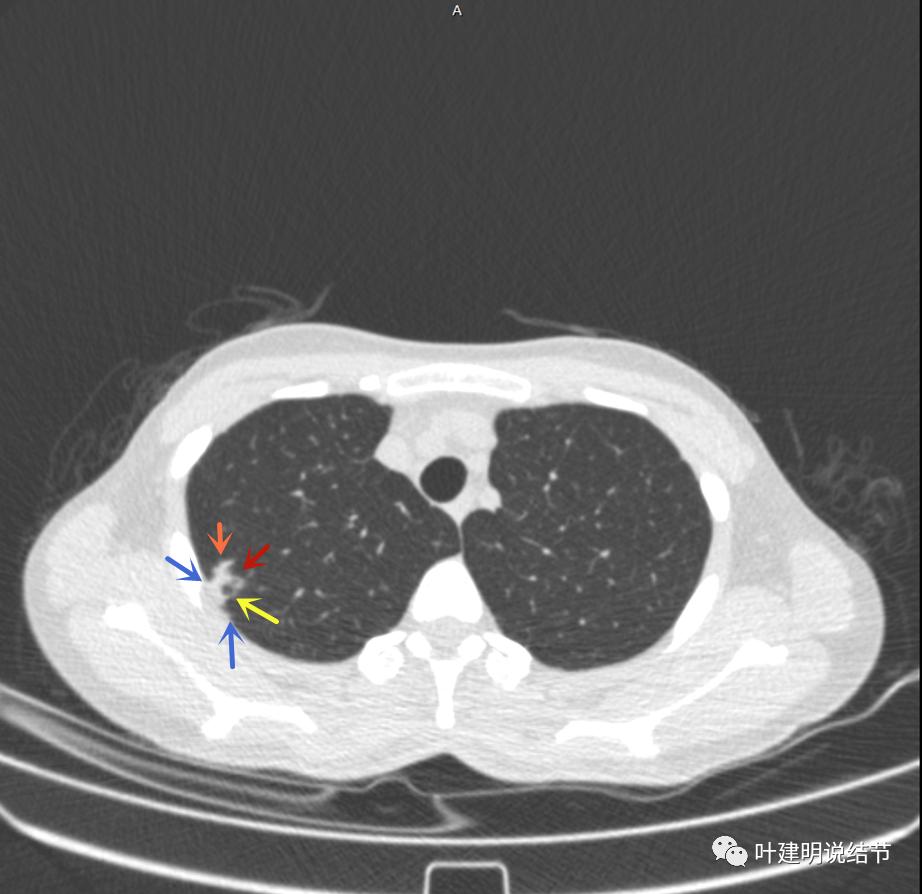

主病灶出现,粉色箭头示病灶密度较高,边上有磨玻璃影,甚淡(砖色箭头)

病灶有空洞(黄色箭头),主病灶边上见条索状高密度影(细红色箭头),邻近胸膜有粘连(蓝色箭头)

邻近胸膜明显增厚,且广基底,主病灶前方有小片磨玻璃影

主病灶与胸膜间基本相连,模糊清(蓝色箭头),主病灶壁厚薄欠均,边上有高密度条索状(桔色箭头)